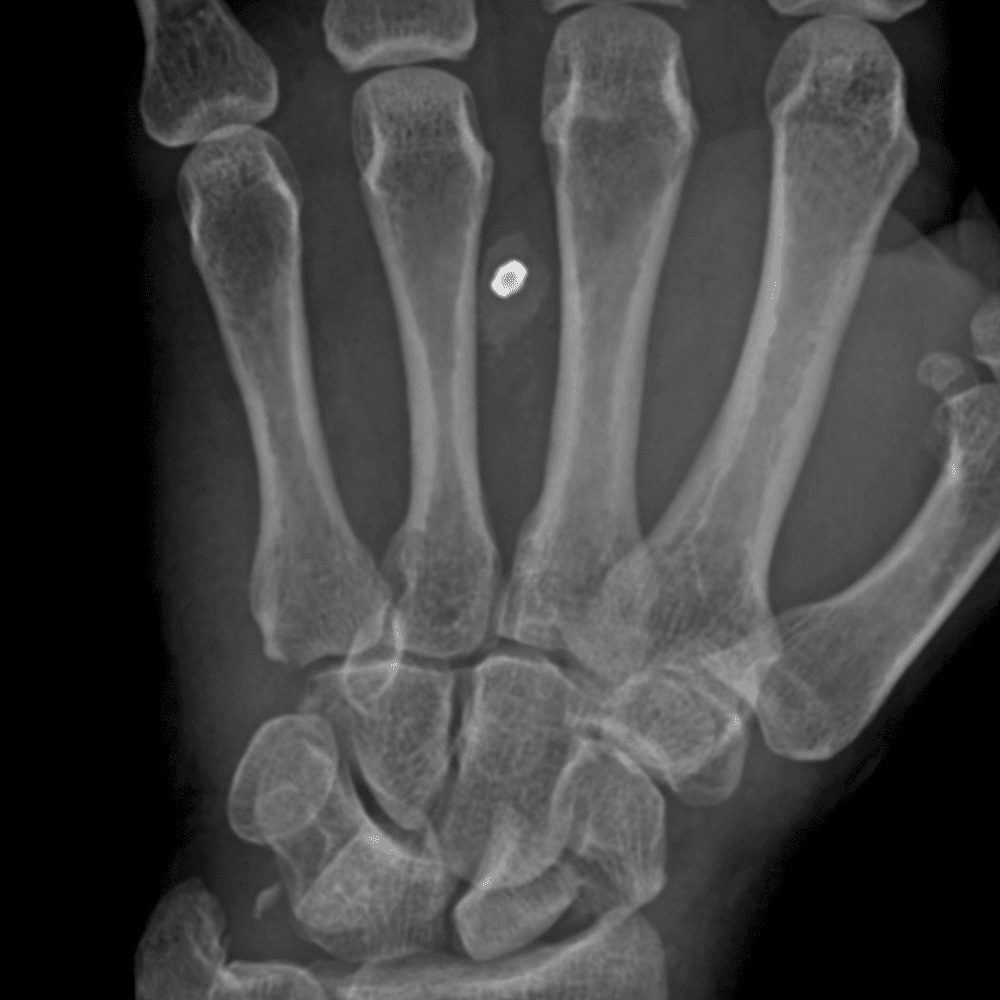

Simuliert den Dienst durch subtile oder schwierige Fälle und einige Normalbefunde.

30 Fälle